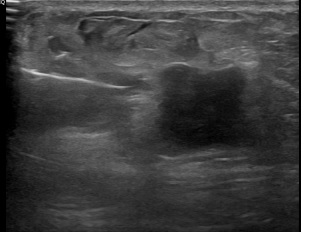

아산유외과개원후 827번째 유방암진단

상기환자는 좌측 만져지는 멍울로 내원하신 60대초반

여성분으로 의심스러운 좌측혹 조직검사 시행해 침윤성암으로 진단되었습니다